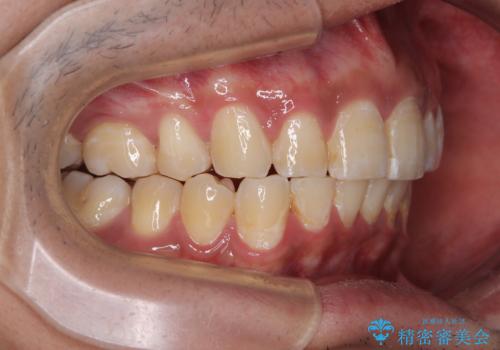

深い咬み合わせと前歯のデコボコ ワイヤー装置での抜歯矯正

- 深い咬み合わせと前歯のデコボコを改善したいとのことで来院された患者様です。

口元の突出感はないものの、上顎前歯のデコボコが著しく、右側の咬み合わせがずれていたため、上顎右側第一小臼歯1本を抜歯することとしました。

咬合力が非常に強く、抜歯したスペースがなかなか閉じないであろうことは予想できましたが、思っていた以上に期間がかかりました。

前歯のすり減りも著しかったため、仕上げの位置の調整にも期間を要しました。